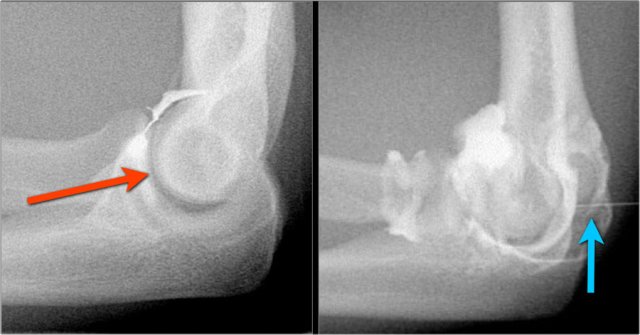

Typically the radiocapitellar joint is punctured from lateral with the patient prone and the arm flexed 90 degrees overhead (red arrow).

This however can sometimes cause problems if you are interested in the lateral ligaments and you inject lidocaine or contrast into these ligaments.

So more recently we started to use the posterior approach into the olecranon fossa (blue arrow).

Diluted gadolinium is injected, i.e. 0,05cc + 10cc saline (an "off-label" use in the US).